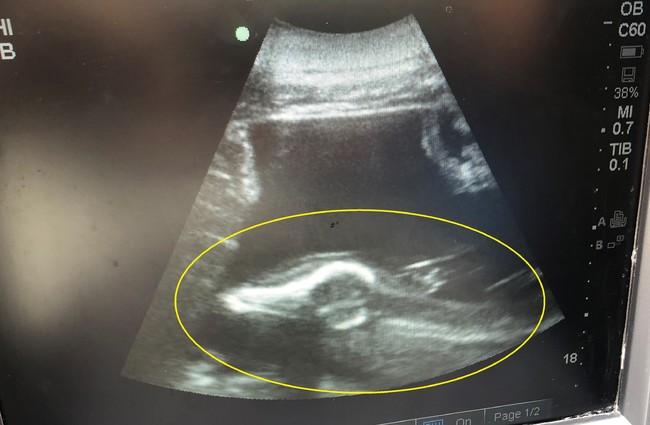

妊娠については、2021年11月初旬に、体調管理のため定期的に行っている血液検査で兆候が示され、その後の超音波検査で胎仔の動きを確認しました。現在妊娠5カ月目に入っており、2022年9月下旬に出産を迎える予定です。なお、父親は赤ちゃんの誕生後にDNA検査を行い特定します。